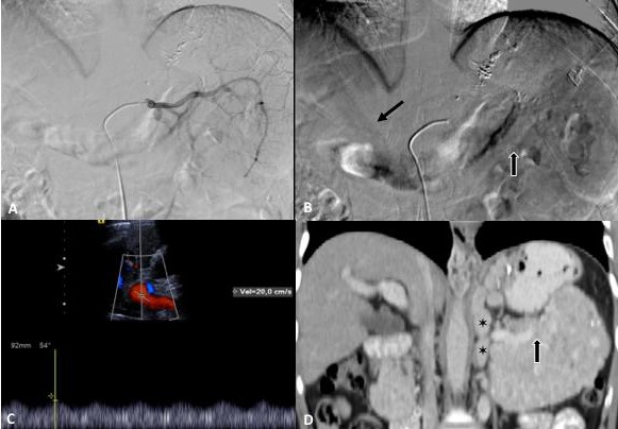

Por ultrasonido se demostró parénquima hepático normal y páncreas con aumento de volumen y ecogenicidad heterogénea. Por tomografía multifásica el páncreas mostró aumento de volumen en su totalidad, precontraste densidad heterogénea con zonas nodulares hiperdensas y calcificaciones, con atenuación promedio de 45UH, realce arterial con atenuación de 86UH, portal 112UH y disminución en fase venosa a 100UH. Además se observó colapso de la porción distal de la vena esplénica y circulación colateral en hilio esplénico, fondo gástrico y periesofágica (Fig. 1 y 2). La medición de gradientes hepáticos y angiografía de tronco celíaco con presión de vena suprahepática libre 12mmHg, presión enclavada 14mmHg, gradiente de 2mmHg, sin evidencia de shunts intrapancreáticos, hallazgos consistentes con hipertensión portal postsinusoidal (Fig. 2).